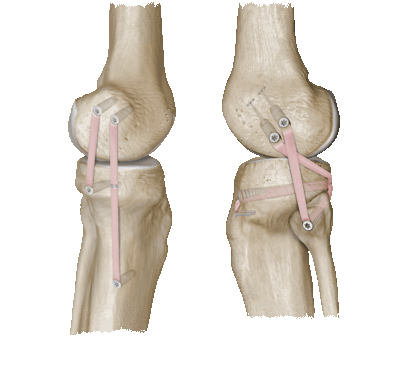

В процессе вмешательства хирург меняет форму костей или их местоположение. Операцию назначают, например, при неправильно срастающемся переломе, врожденных или приобретенных патологиях костей. После операции больной остается в медучреждении в течение нескольких дней, получая обезболивающие. Первые упражнения начинаются еще в этот период, чтобы не допустить образования тромбов. Если самостоятельно разрабатывать сустав не получается, можно воспользоваться специальными тренажерами.

Первые несколько недель рекомендовано ношение гипсовой повязки, чтобы обеспечить покой суставу. Для перемещения надо использовать костыли либо инвалидную коляску, так как переносить вес на прооперированную ногу запрещено. После снятия гипса подвижность возвращается медленно, но это служит одним из признаков удачной реабилитации.

Комплекс упражнений, способных вернуть суставу подвижность, обычно включает:

- сгибания ног из положения лежа;

- подъем прямой ноги с натянутым на себя носком из положения лежа или сидя;

- подъем ягодиц из положения лежа с согнутыми в коленях ногами;

- приподнимание на носках у опоры.